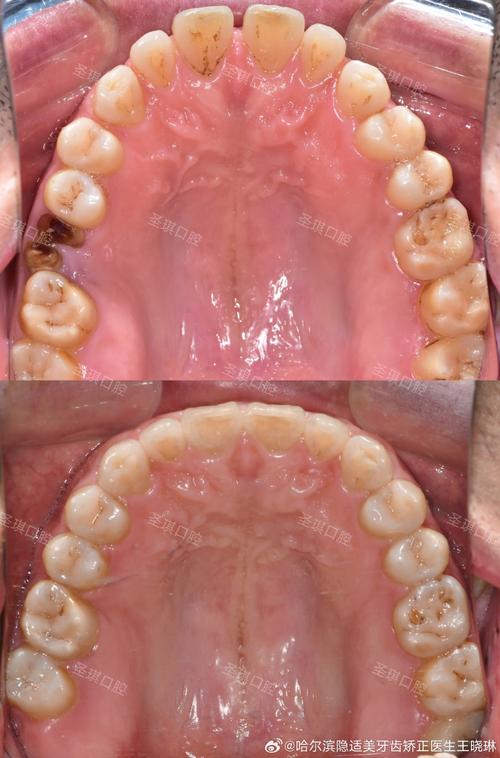

(图片来源网络,侵删)- 拔除智齿为正畸创造空间: 有时,为了给前牙或前磨牙的排齐提供空间,正畸医生会建议拔除前磨牙(通常是第一前磨牙)或部分磨牙,在极少数情况下,如果智齿位置相对正常且有足够空间,有时会保留智齿替代拔除的磨牙,但这需要非常严格的评估。